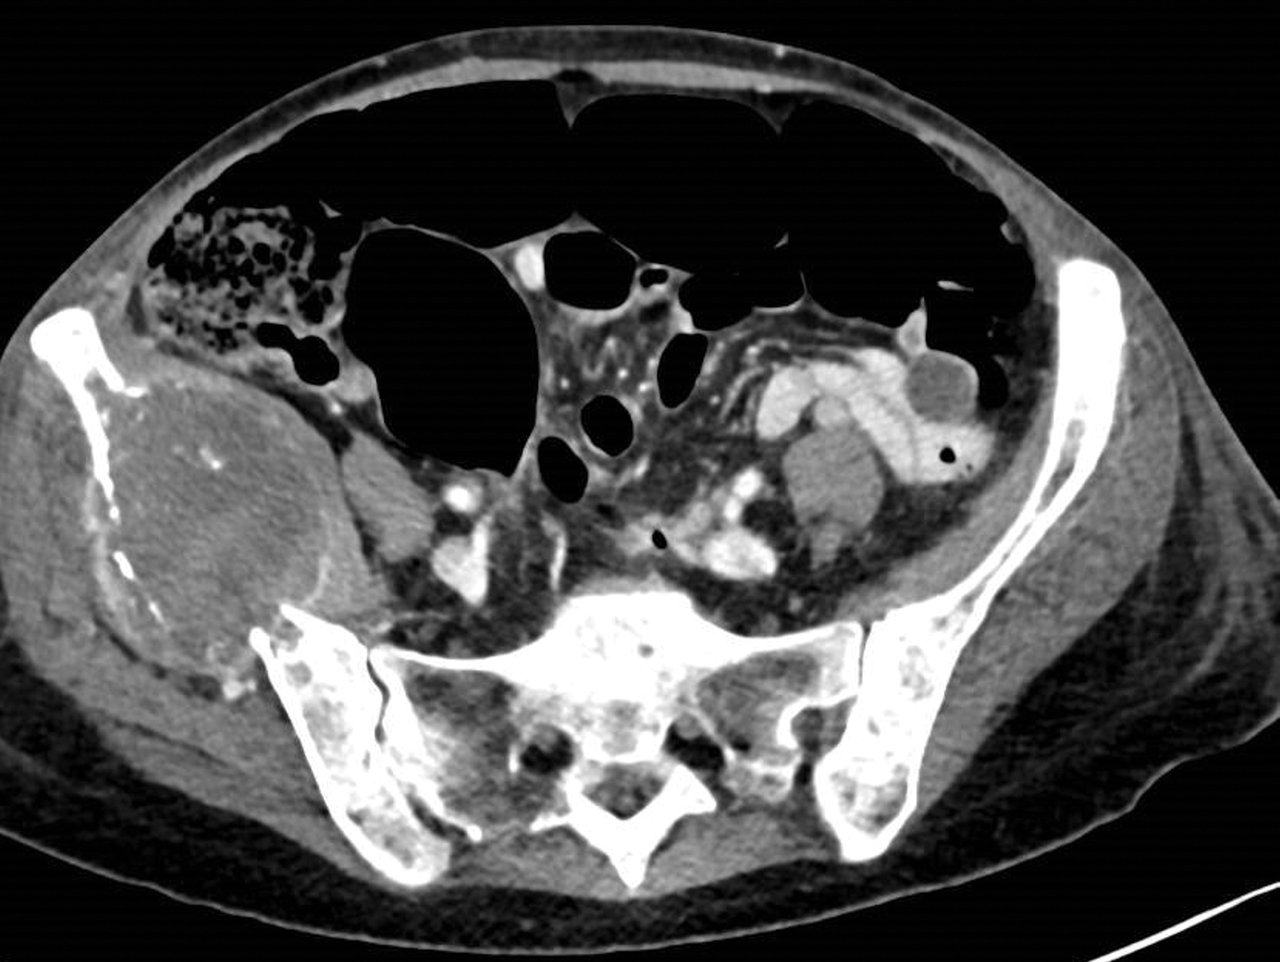

Femme 72 ans, tabagique sevrée consultant pour des douleurs du bassin depuis 1 mois, avec altération de son état général.

Quel est votre diagnostic ?